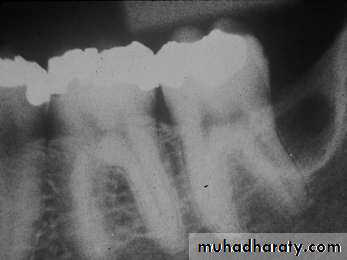

• Radiography:• Uni or Multilocular radiolucent areas

• Soap bubbles

• Copyright 2003, Elsevier Science (USA). All rights reserved.• Ameloblastoma

• Radiography:

• Soap bubbles appearance